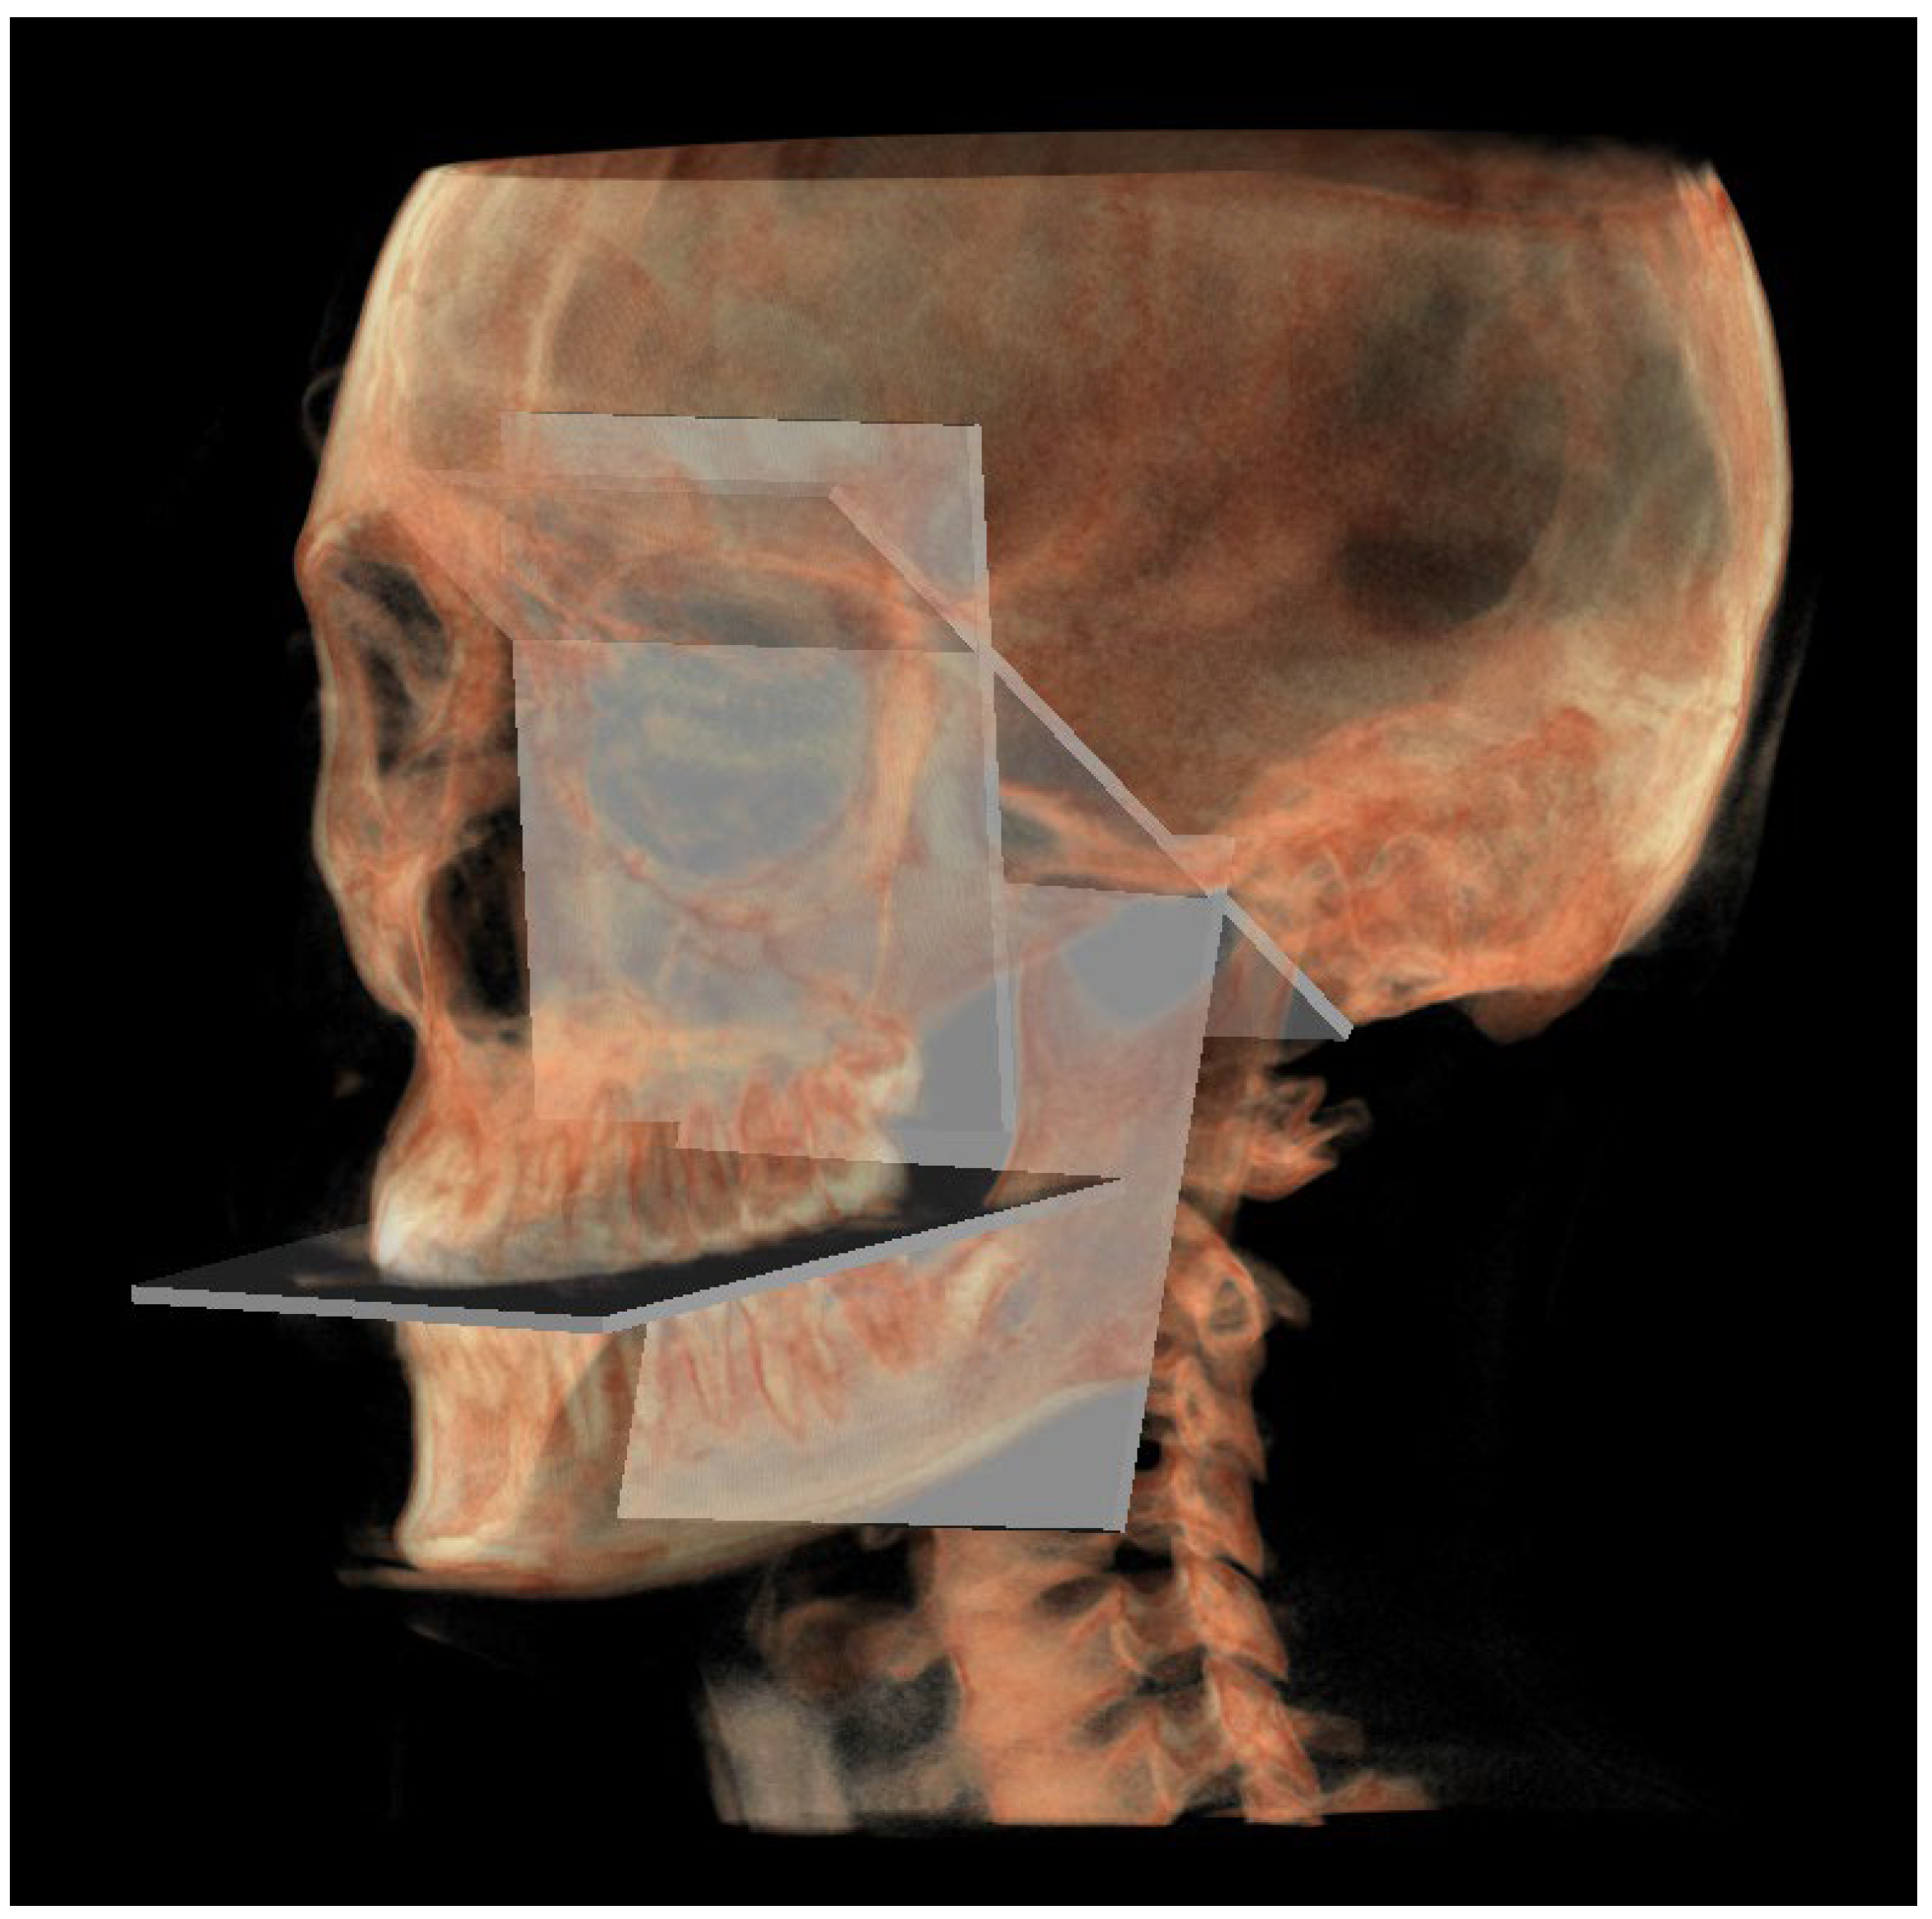

- PM (Figure 4) was identified by the points lMCF, rMCF and posterior nasal spine (PNS);

- The mandibular ramus plane (MR) (Figure 5) was identified by the following points: the middle points between the right and left condylion (mCo) and the right Gonion (rGo) and left Gonion (lGo). To adequately locate the mCo, it is advisable to draw a line on the frontal view from the right condylion to the left one to have a reference along which measure the mid-distance;

- The functional occlusal plane (FOP) (Figure 6) was identified by the posterior occlusal contact right side (rPoc), posterior occlusal contact left side (lPoc) and the middle point between the right and left anterior occlusal contact (mAoc). To adequately locate the mAoc, it is advisable to draw a line on the transversal view from the right mesial premolar contact to the left one to have a reference along which measure the distance.